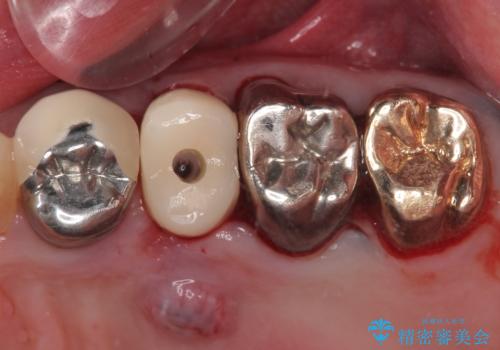

破折した奥歯 抜歯即時埋入インプラントによる補綴治療

- 舌側に膿の出口がずっと消えずに有り続けることを気にして来院された患者様です。

目視で歯根が破折していることが分かり、保存不可能と判断されたたため、抜歯即時埋入インプラントによる補綴治療を行うこととしました。